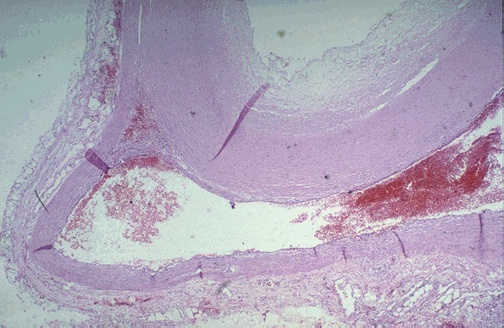

| Here, the aortic dissection went into the muscular wall of the aorta. In any case, an aortic dissection is an extreme emergency and can lead to death in a matter of minutes. The blood can dissect up or down the aorta. Blood dissecting up around the great vessels can close off the carotids. Blood could dissect down to the coronary arteries and shut them off. |